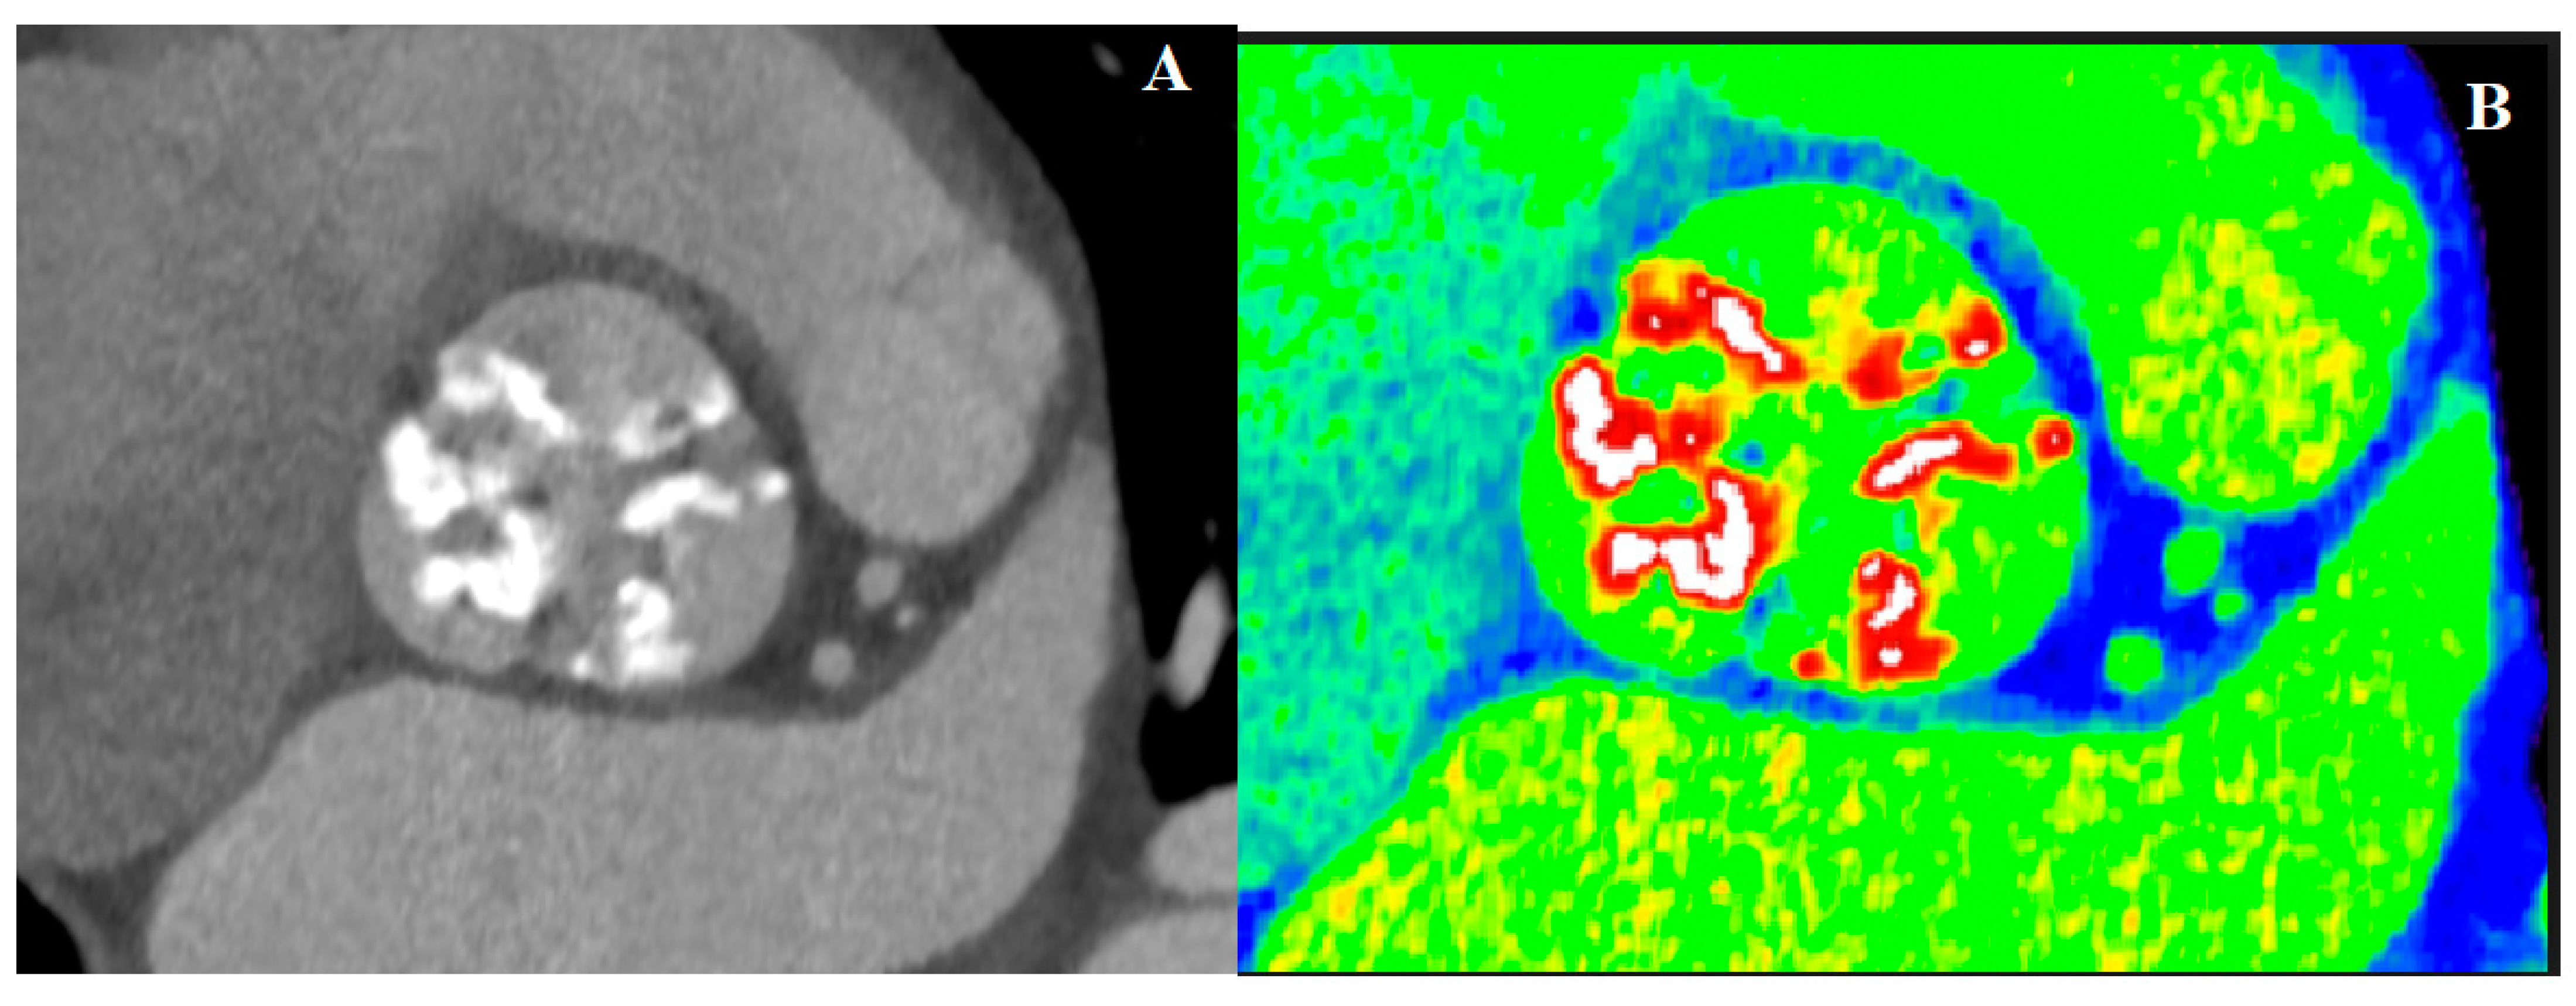

4.2. Computed Tomography in AS